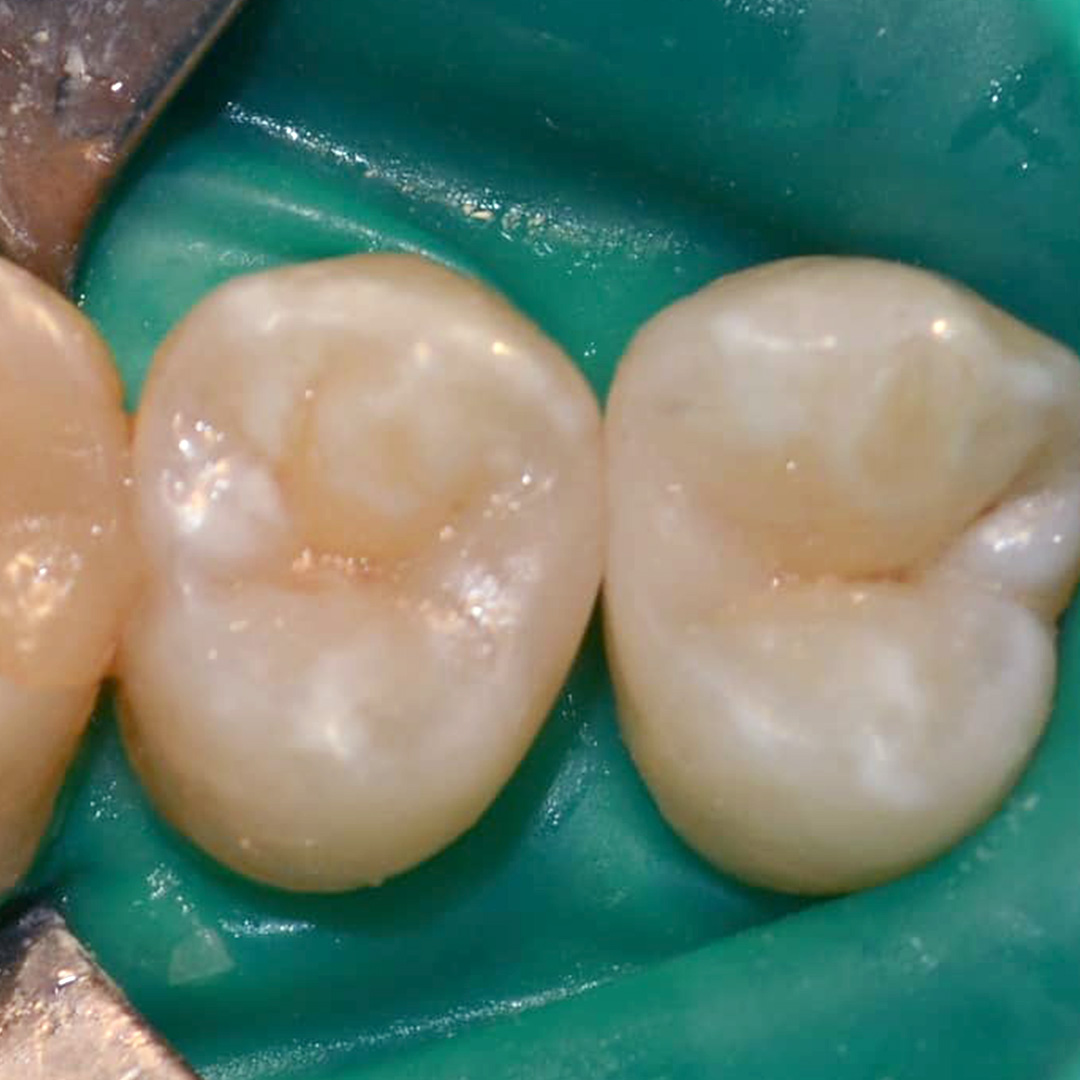

До и после лечения

В нашу клинику обратилась пациентка, которую беспокоили болевые ощущения слева сверху во время приёма сладкой или кислой пищи. В процессе осмотра и диагностики было установлено, что причиной болей и дискомфорта является хронический средний кариес 14, 15 зубов.

Процесс работы

Ход работы:

- применение инфильтрационной анестезии;

- механическая обработка кариозной полости с использованием коффердама;

- пломбирование светокомпозитным материалом;

- микроконтурирование и макроконтурирование пломбы.